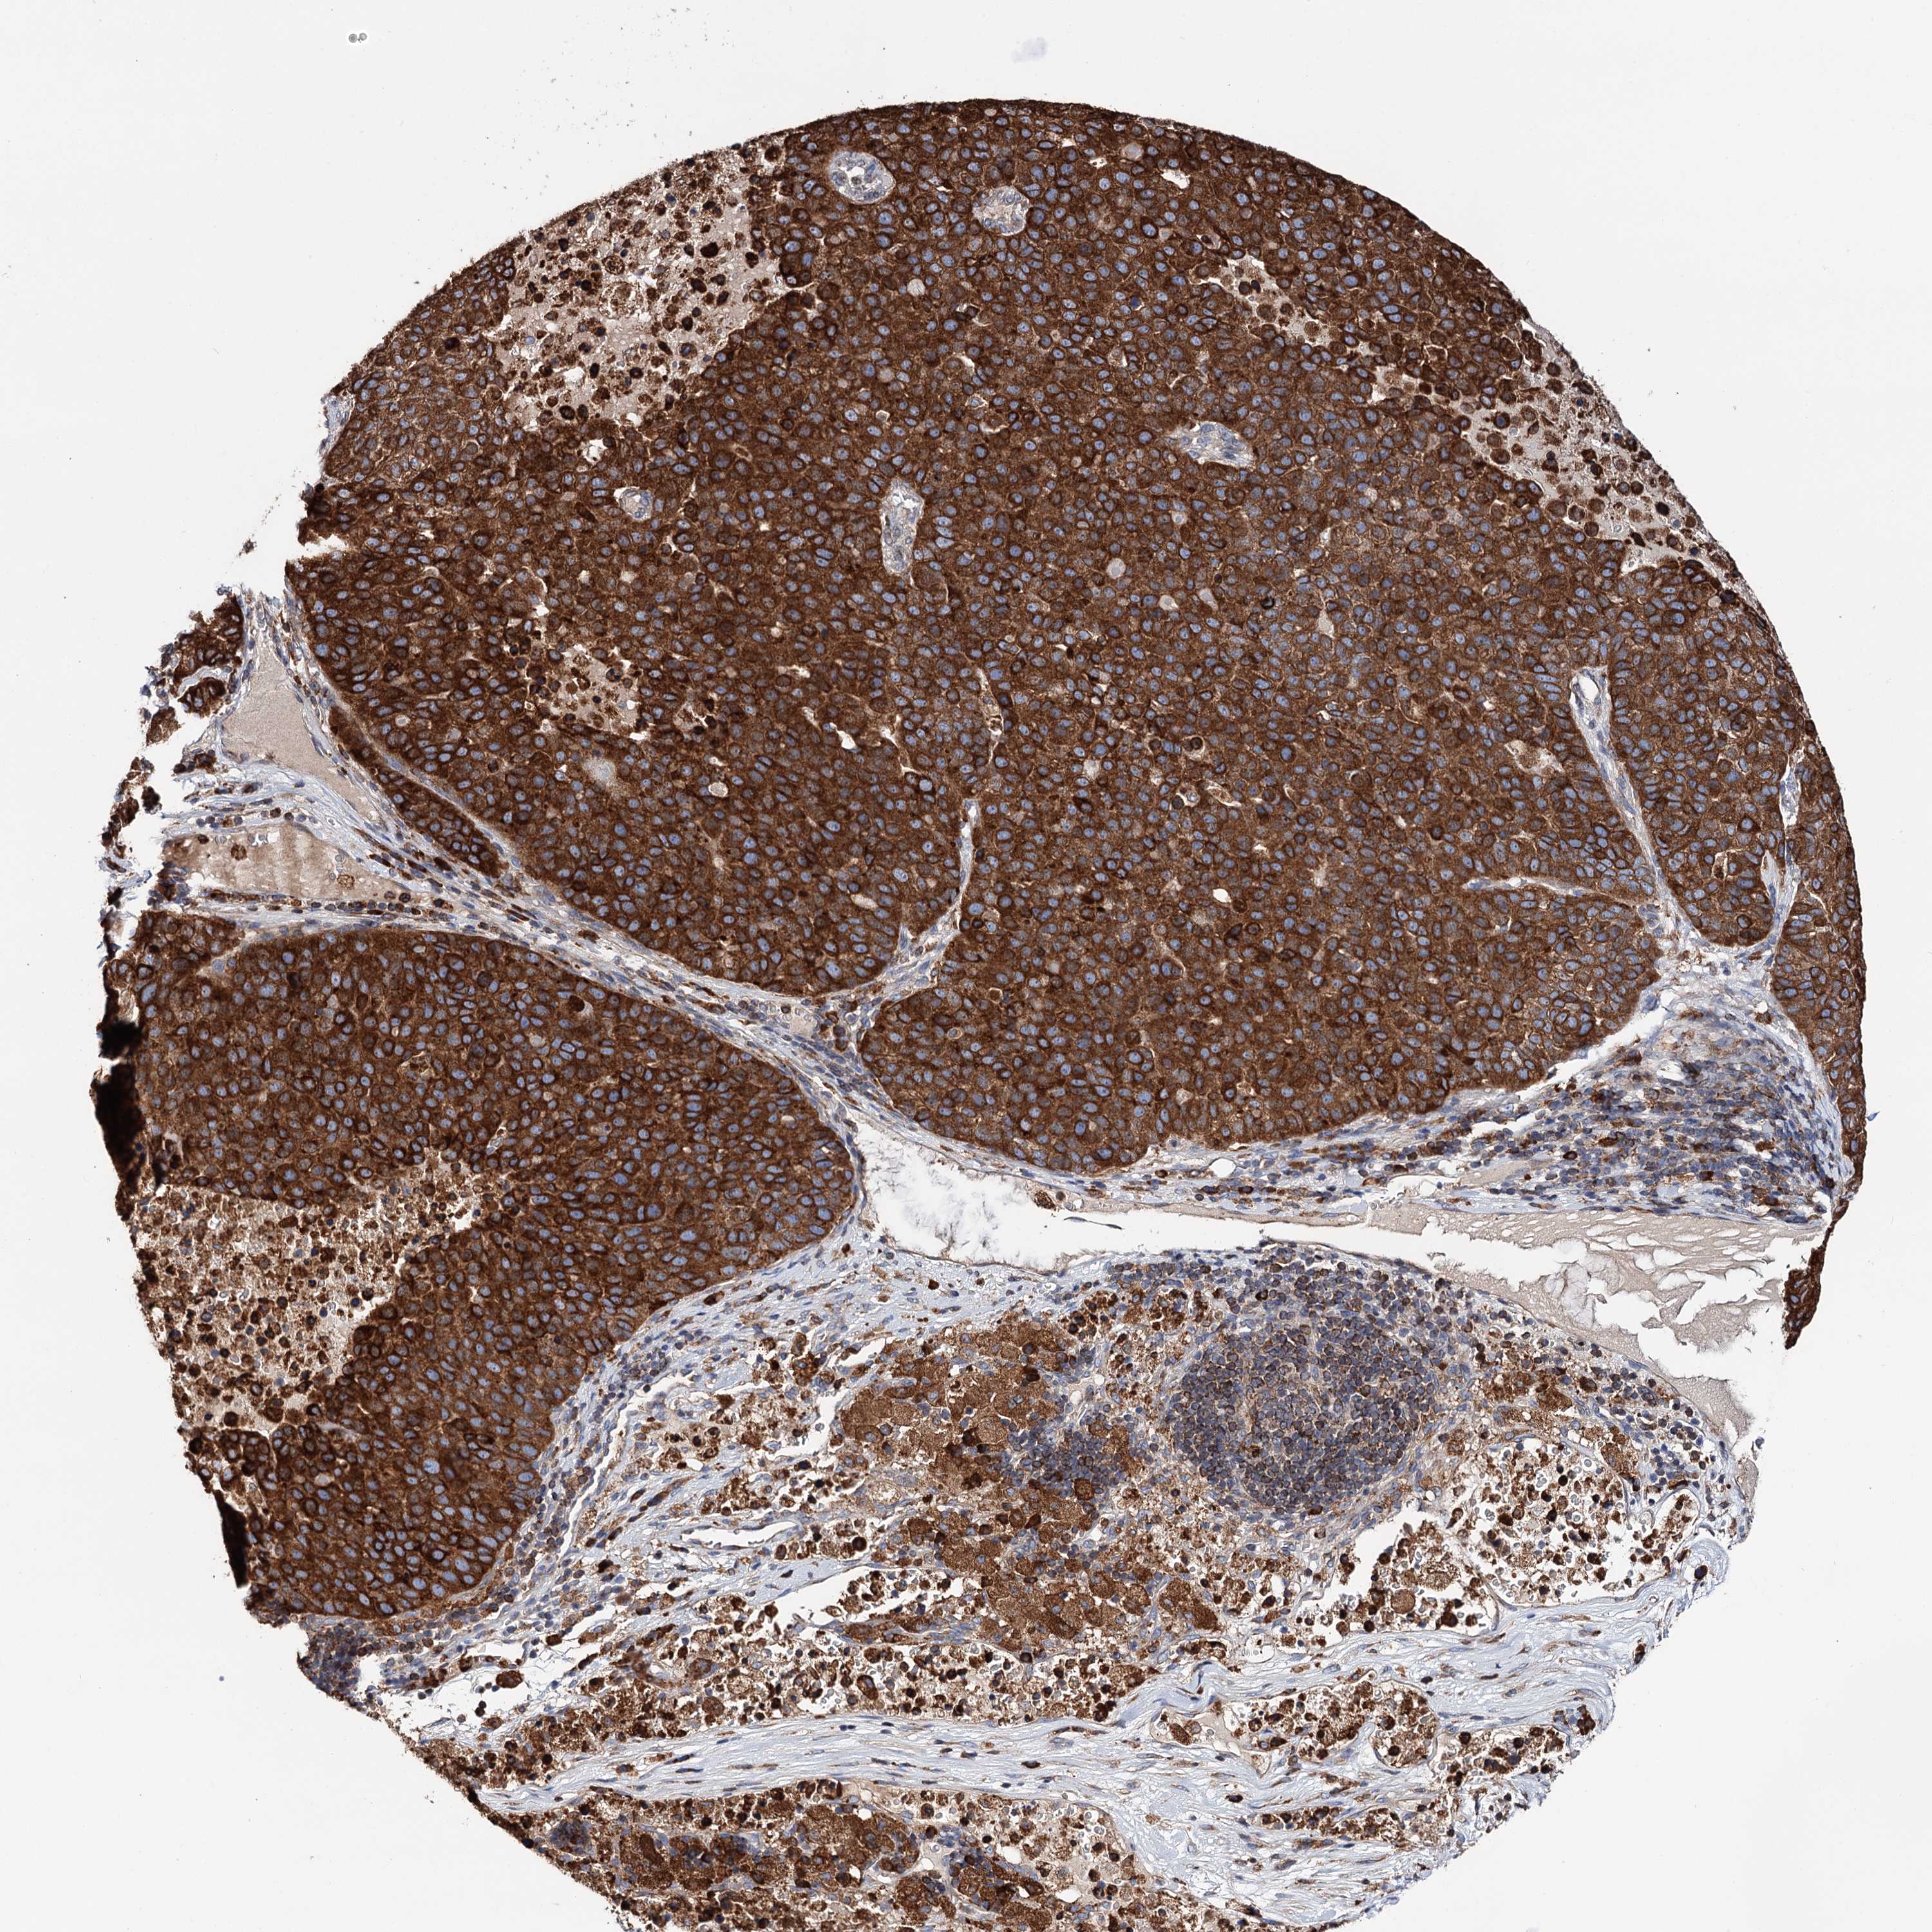

PANCREATIC CANCER - Protein expressioni

A mouse-over function shows sample information and annotation data. Click on an image to view it in a full screen mode. Samples can be filtered based on level of antibody staining by selecting one or several of the following categories: high, medium, low and not detected. The assay and annotation is described here.

Note that samples used for immunohistochemistry by the Human Protein Atlas do not correspond to samples in the TCGA dataset.

Antibody stainingi

Antibody staining in the annotated cell types in the current human tissue is reported as not detected, low, medium, or high, based on conventional immunohistochemistry profiling in selected tissues. This score is based on the combination of the staining intensity and fraction of stained cells.

Each image is clickable and will lead to virtual microscopy that enables deeper exploration of all samples and also displays staining intensity scores, fraction scores and subcellular localization as well as patient and tissue information for each sample.

Antibody HPA039363

Antibody HPA039456

Adenocarcinoma, NOS